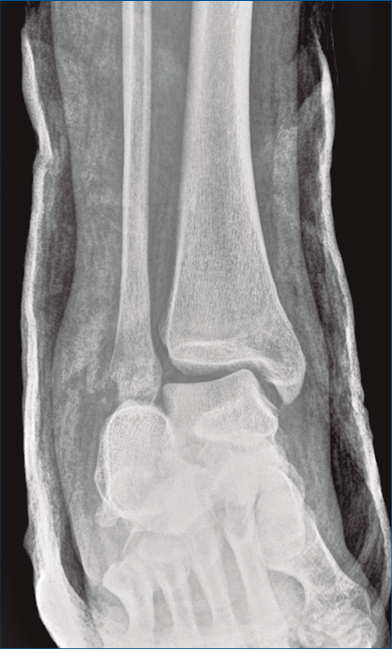

Figura 9. Control radiográfico posquirúrgico, anteroposterior.

Se dio de alta el día siguiente a la cirugía con un buen control analgésico. En la radiografía de control postoperatoria presentó una correcta reducción tanto de la fractura de calcáneo como de la articulación tibioperoneo astragalina (Figuras 9 y 10). Se citó en consultas externas 2 semanas después para la retirada de la sutura, presentado un buen aspecto las heridas quirúrgicas (Figura 11), y para la colocación de un botín de yeso. Dicho botín fue retirado al mes y medio de la cirugía, colocándose una ortesis estabilizadora de tipo Walker y autorizándose la carga parcial y progresiva, comenzando la rehabilitación.